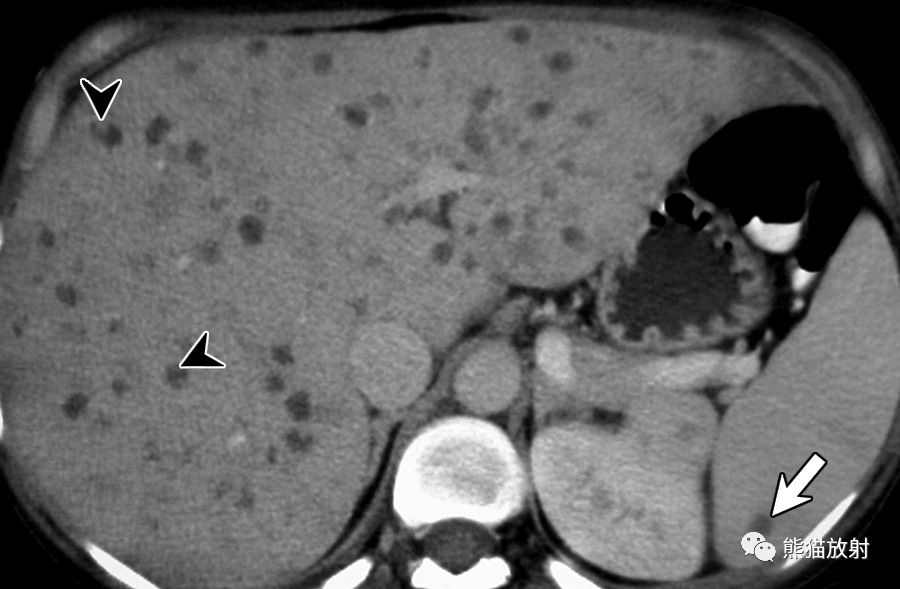

中性粒细胞减少症和急性髓系白血病患者发生播散性念珠菌病。对比增强CT图像显示多发性低密度肝微脓肿。在一些脓肿中可见密度增加的微小病灶(箭头),可能代表假菌丝,这一发现有助于区分这些病变与良性肝囊肿。注意脾受累(箭)。

播散性念珠菌病,中性粒细胞减少症患者在造血干细胞移植后34天出现发热。(a)脂肪抑制T2WI图像显示肝内散在多发小的中等高信号结节(箭头)。(b) DWI (b=800s/mm2) 显示真菌病灶扩散受限呈高信号(箭)。(c) 脂肪抑制T1WI仅显示一些较大结节,呈低信号(箭头)。(d) 对比增强动脉期脂肪抑制T1WI图像显示多发边界不清的明显强化肝结节(箭)。动脉期CT或MR图像可在早期描述更多的病灶,尤其是在病灶中央坏死出现之前。